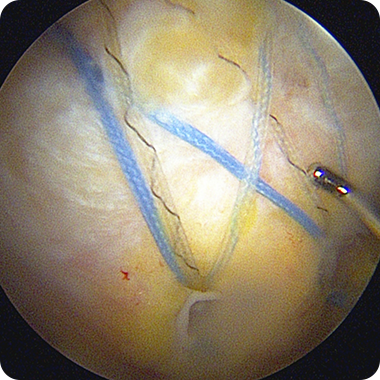

회전근개봉합술은 1cm 미만의 수술 부위로 특수 관절내시경 장비를 이용해

파열된 힘줄을 봉합하는 최소침습 수술입니다.

고해상도 내시경으로 손상 부위를 직접 보며 수술하기 때문에

정확도는 높고, 통증과 회복 부담은 현저히 줄어듭니다.

1cm 미만의 절개로 관절내시경을

삽입해 회전근개 파열 부위를

직접 확인합니다.

특수 앵커와 봉합사를 이용해

끊어진 힘줄을 본래의 위치로

단단히 고정합니다.

봉합 상태를 내시경으로 확인한 뒤

절개 부위를 봉합하고

수술을 마무리합니다.